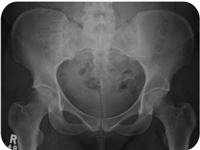

Digital Xray

High Quality x-ray which gives Enhanced images with the scope of digital transfer. Avail best in class X RAY Service with DR system in Lifecare Scan & Research Centre at Durg & Bhilai.